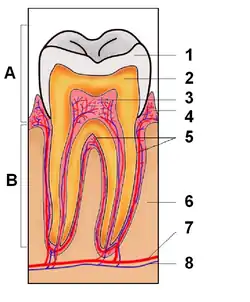

A. Krone

B. Rod

1. Emalje

2. Dentin

3. Pulpa

4. Gumme

5. Rodcement

6. Knogle

7. Blodåre

8. Nerve

Tanden er en modificeret papil, som stammer fra mundens slimhinde og som dækkes af kalcificerede substanser.